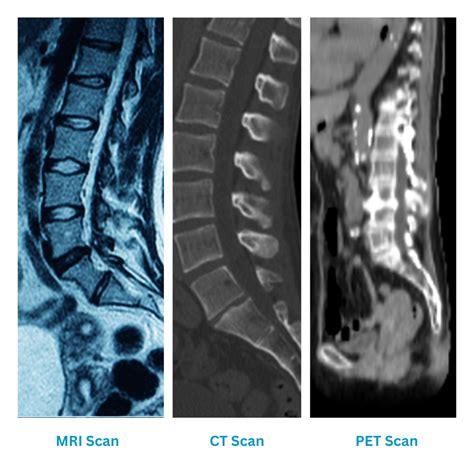

Physicians typically use a combination of physical examinations and advanced imaging to confirm these symptoms. If you report persistent back pain that does not respond to conventional physical therapy, your healthcare provider may suggest the following diagnostic sequence:

• MRI Imaging: The gold standard for visualizing the spinal cord and soft tissue.

• CT Scans: Used to assess bone integrity and look for structural changes caused by the tumor.